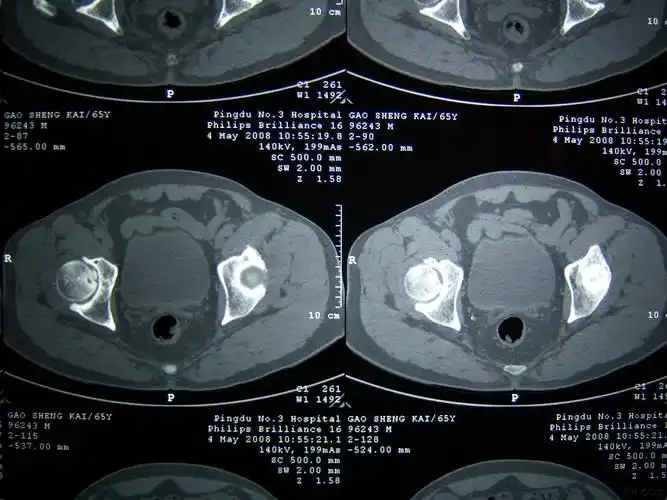

【讨论】盆腔ct平扫 增强

后行盆腔ct检查:盆腔畸形占位.

ct00021盆腔占位